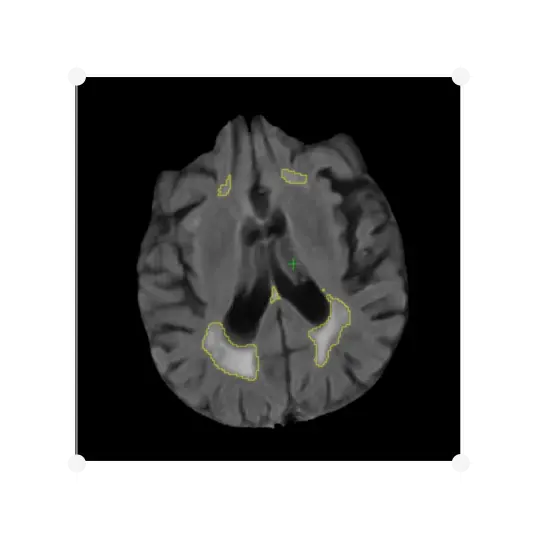

The identification of WMH is highly relevant to a dementia diagnosis, and is a criterion for the exclusion of subjects participating in a clinical trial, as well as a measure of treatment efficacy. IXICO provide a visual read to screen subjects with severe vascular pathology. IXICO can accurately quantify the volume of WMH using IXICO's automated methods, assessing a subject’s 3D T1W and FLAIR MR images.

IXICO's analysis delivers the volume of white matter, the volumes of hyperintense lesions, and the percentage of white matter hyperintensity. It can be applied to five regions of interest:

• Whole white matter

• Juxtaventricular

• Periventricular

• Deep white matter

• Juxtacortical

IXICO's method uses tissue classification and hyperintensity belief maps that are iteratively grown by analysing neighbouring voxels, and provides improved robustness to discriminate subjects with significant white matter pathology, with good correlation with Fazekas scoring and manual volumetry.